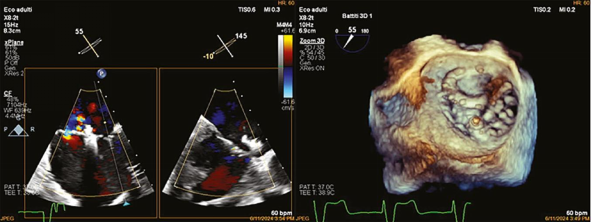

术后随访

1个月随访显示心功能稳定,6个月时LVEF恢复至>60%,左室缩短分数>0.35,肺动脉收缩压35 mmHg。患者恢复日常活动(如长距离骑行),无疲劳或呼吸困难,药物方案调整为利尿剂、ARNI(沙库巴曲/缬沙坦)、SGLT2抑制剂(恩格列净)等。

病例讨论与启示成形环脱位是二尖瓣修复术后罕见但严重的并发症,常因缝线断裂、感染或长期血流冲击导致。传统处理需开胸手术(更换成形环或行瓣膜置换),但二次手术死亡率高达10%-15%。本病例通过经皮介入成功规避了开胸风险,凸显TMVR在高危人群中的替代价值。与MitraClip相比,PASCAL系统的“Spacer”设计可填充瓣叶间隙,独立抓取臂(“Clasp”)允许分步夹合,更适合解剖复杂的病例(如脱位环遮挡或钙化瓣叶)。本病例中,术者利用TEE实时三维成像精准导航,将装置置于脱位环下方,避免了器械干扰,体现了影像引导的关键作用。